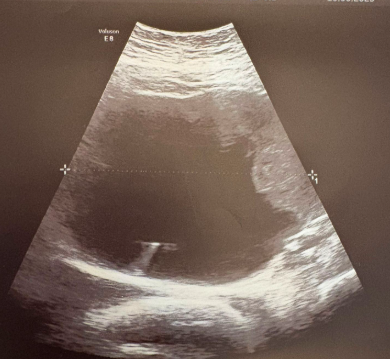

Realizamos ecografía abdominal clínica donde apreciamos en zona referida imagen quística, de contenido mixto de 11 centímetros, sin poder precisar si depende de útero u ovarios. Resto sin alteraciones reseñables. Derivamos a hospital de referencia para completar estudio.

En hospital de referencia, se realizan ecografía vaginal observando imagen quística en ovario izquierdo de gran tamaño.